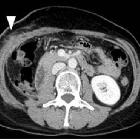

Imaging

spectrum of abnormal subcutaneous and visceral fat distribution. A 59-year-old woman with post-surgery lipoatrophy. a CT image before operation shows calcified soft tissue density mass anterior to the right kidney (arrow). Right nephrectomy was done, and the lesion was pathologically diagnosed as dedifferentiated liposarcoma. b CT image one month after surgery shows fluffy opacity in the subcutaneous fat around the operated area (arrowhead) with abdominal wall muscle swelling. c CT image after 8 years shows local lipoatrophy (double arrow) with muscle atrophy